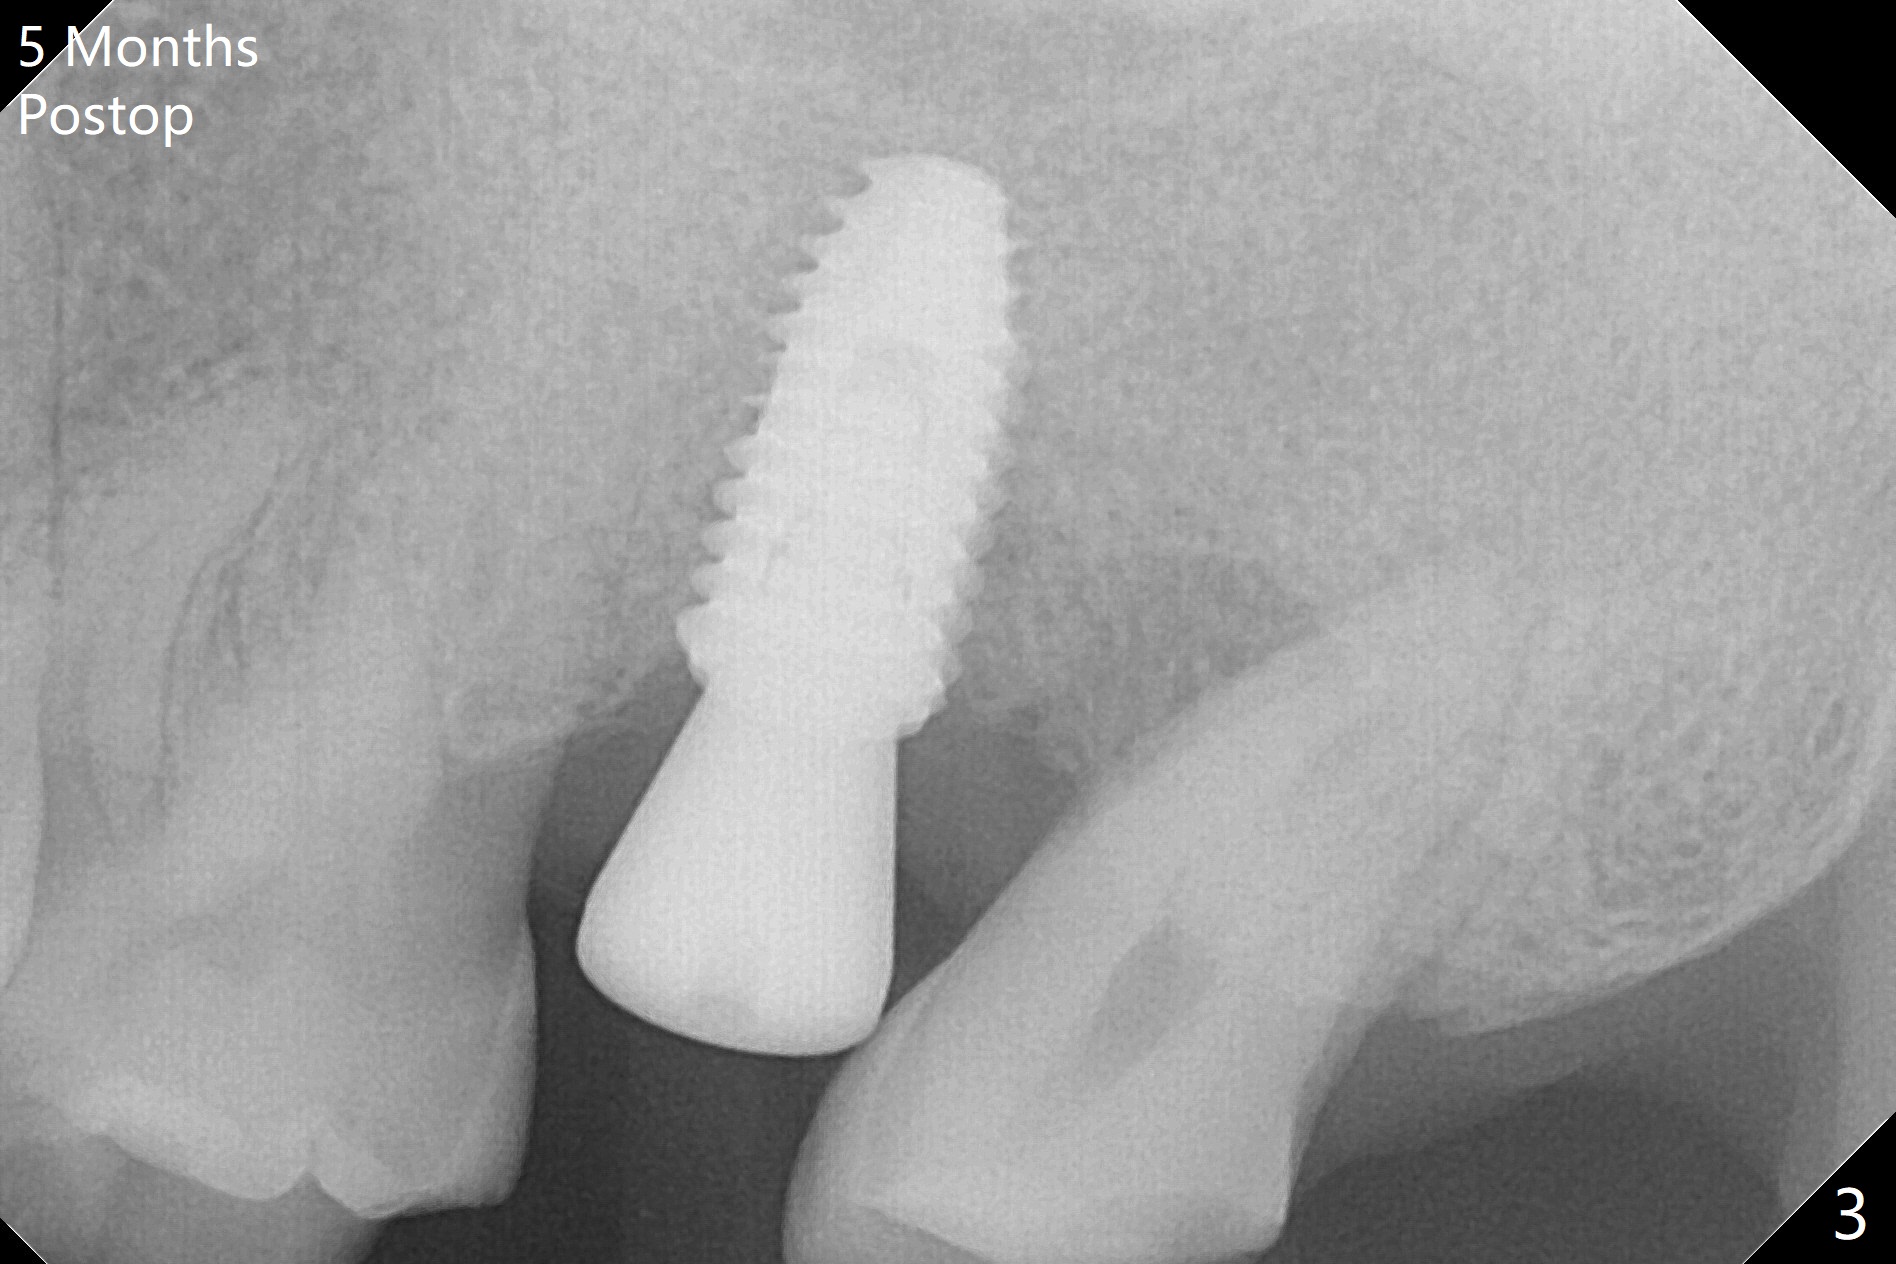

For the narrow mesiodistal space (Fig.3), a 4.5x4.5(3) mm cementation abutment is placed for final restoration. He expresses interest in implants at #29 and 30 or #19. The screw is loose 2 years 5 months post cementation; the crown/abutment is incompletely seated after proximal reduction of the crown (Fig.4). Due to the narrow space, a new abutment appears to be easier to be seated (Fig.5). When the permanent crown is delivered, the distal contact is loose, probably related to ill-fitting temp. The permanent crown is cemented with temp bond. Return to Upper Molar Immediate Implant, Armaments, Guide for 29/30 Torque Xin Wei, DDS, PhD, MS 1st edition 05/11/2018, last revision 04/19/2021